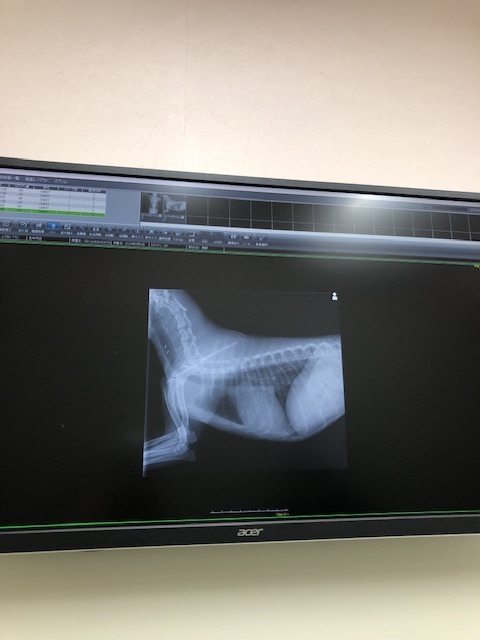

(心臓のエコー写真を見ながら)心臓の様子も何かあるようには見えないし、